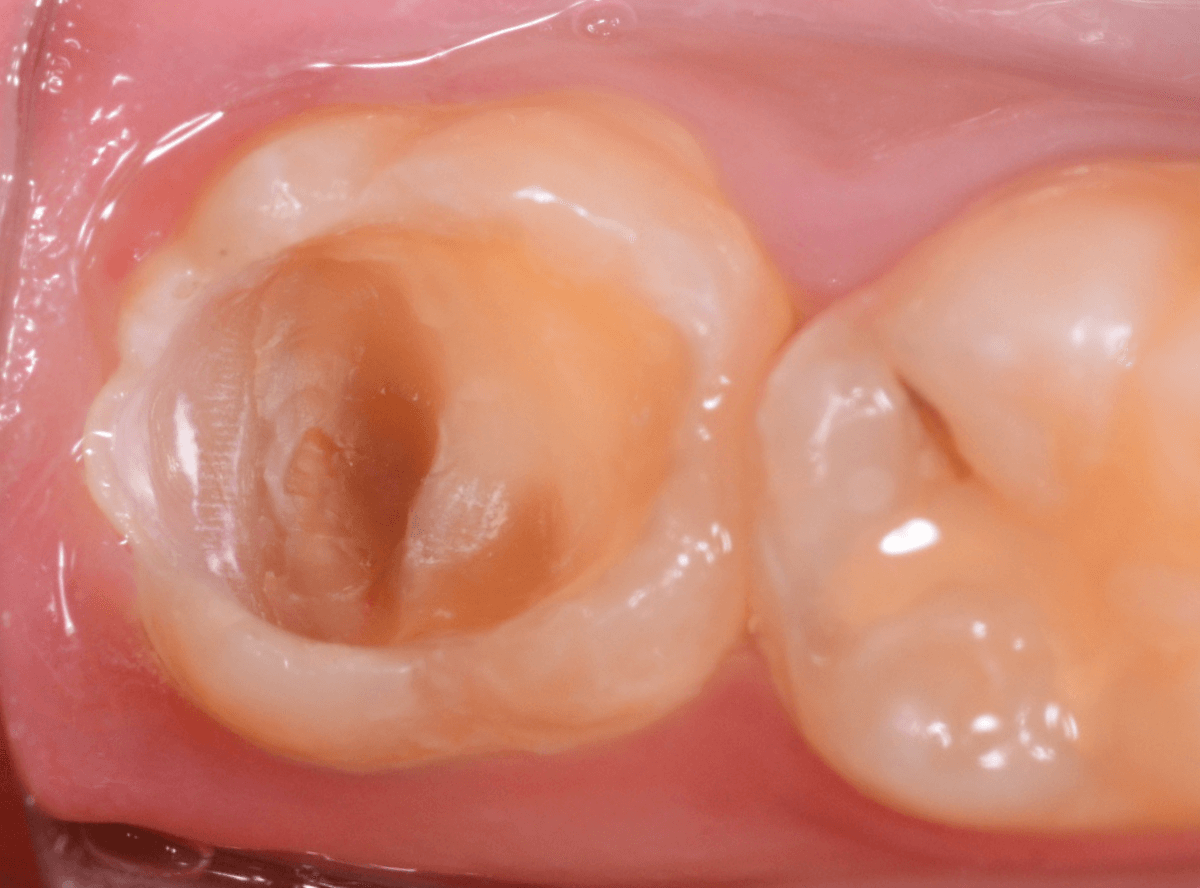

Case.15 レジンの下の深い虫歯

奥歯で咬んだ時に、痛みを感じるという訴えで来院された患者さんです。

パッと見は特に問題なさそうな状態ですが、大きなレジン治療がしてあり、レジンの奥もボヤっと黒っぽく見えてアヤシイ感じです。

麻酔をして、レジンを外します。

レントゲン写真から想定できるような大きな虫歯ですね。

慎重に虫歯を除去します。

赤く染色されている部分が虫歯の残っている部分です。

全ての虫歯を除去したところです。

何とか神経の寸前で虫歯を食い止める事ができましたが、まれに症状が出る事もありますのでお薬をつめてしばらく経過観察します。